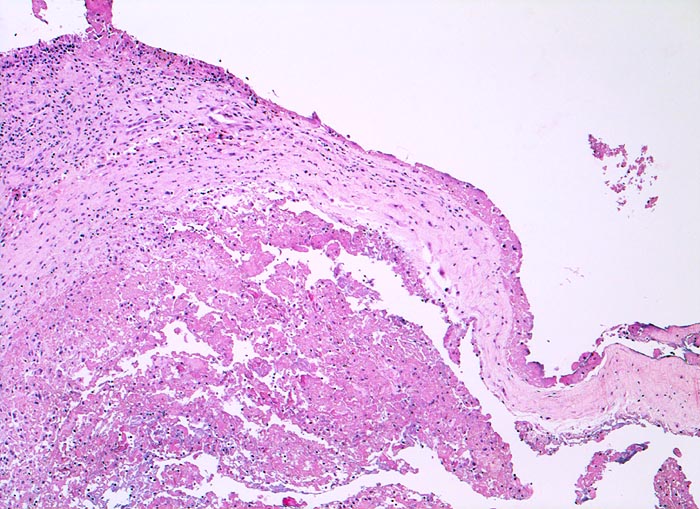

In Abhängigkeit von der Entzündungsdauer werden unterschiedliche morphologische Befunde beschrieben. Die initiale proliferative Phase ist charakterisiert durch eine Hyperplasie der Synovialis, Fibrinexsudate und Gelenkergüsse. In der destruktiven Phase kommt es zur Zerstörung von Gelenkknorpel und gelenknahem Knochen durch Ausbildung eines intraartikulären Pannusgewebes (> 194). Die ausgebrannte Phase ist gekennzeichnet durch eine synoviale Fibrose mit zunehmender Ankylose (= Gelenkversteifung).

Typische histologische Veränderungen sind eine synoviale Zottenhyperplasie, Verbreiterung der Deckzellschicht unter Einschluss mehrkerniger Riesenzellen, Fibrinexsudate und synoviale Ulzerationen, Infiltrate von Lymphozyten teils in Form von Lymphfollikeln, Plasmazellen, neutrophilen Granulozyten, Makrophagen und Siderophagen, sowie Einschlüsse von Knorpel- und Knochenfragmenten (Detritussynovialitis). Die histologischen Befunde der Synovialis korrelieren oft nicht mit den klinischen Angaben. Trotz fortgeschrittener Gelenkdestruktion mit ausgeprägter klinischer Symptomatik können Synovialektomiepräparate nur sehr geringe pathologische Veränderungen zeigen. Oft ist auch nicht mehr zu eruieren, welche Läsionen Folge der Grundkrankheit und welche Folge diverser intraartikulärer Therapien oder begleitender Superinfektionen sind.

• Herdförmig Fibrinauflagerungen durchsetzt von neutrophilen Granulozyten.